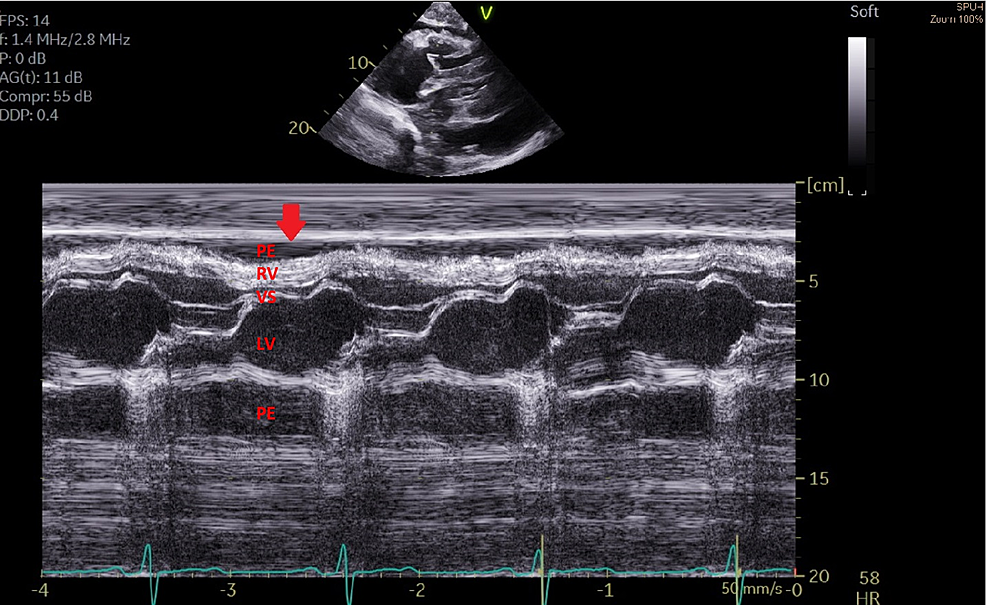

Tamponade M Mode. Transthoracic echocardiography for pericardial effusion. Note how the inward movement of the.

Transthoracic echocardiography for pericardial effusion. Note how the inward movement of the.

Tamponade M Mode Note how the inward movement of the. Transthoracic echocardiography for pericardial effusion. Note how the inward movement of the.